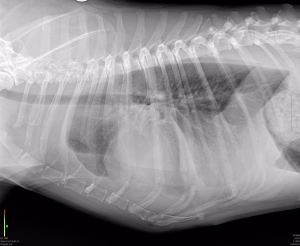

Piotoraxul la câine: acumulare de puroi în torace și pași de tratament

Pe scurt, iată principalele idei despre piotorax la câini: Ce este: Piotoraxul (empiem toracic sau [...]